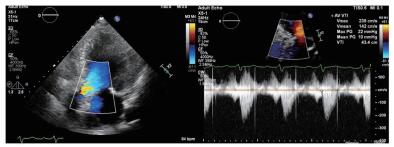

2 实例分析案例:病史摘要:患者为70岁老年女性,因“反复胸闷气促3月余,再发加重3 d”入院。患者2020.3.10从本科急诊途径入院,入院时呈端坐呼吸,伴大汗,本科急诊医生快速完成新冠肺炎核酸检查及肺部CT检查排除新冠肺炎感染后收住心内科监护室。患者既往病史复杂,高血压20年余,糖尿病20年余,2年前曾因冠心病在当地医院行经皮冠状动脉介入(percutaneous coronary intervention,PCI)治疗。入院查体:神清,精神软,呼吸急促,无法平卧,口唇无发绀,颈静脉无怒张,两肺听诊闻及大量湿啰音,心率98次/min,律齐,主动脉瓣听诊区可及4/6级舒张期吹风样杂音,双下肢可见凹陷性水肿。入病房后相关检查提示:“氨基端B型利钠肽原>35 000 pg/mL,肌钙蛋白T 0.139 ng/mL,血肌酐192 μmol/L,血气分析:二氧化碳分压44.7 mmHg(1 mmHg=0.133 kPa)、氧分压65.5 mmHg、氧饱和度90.1%”,心超提示“左室舒张末期内径(LVEDD)5.81 cm,simpson's测得LVEF 33.5%;主动脉瓣呈三叶结构,瓣叶增厚明显,主动脉瓣口最大射流速4.39 m/s,最大压差77 mmHg,平均压差41 mmHg,瓣口面积0.57 cm2” (图 1)。临床诊断考虑:①心脏瓣膜病:主动脉瓣重度狭窄急性心功能不全Killip Ⅲ期;②冠状动脉粥样硬化性心脏病PCI术后;③高血压病;④ 2型糖尿病糖尿病肾病。予以静脉呋塞米利尿等对症治疗后症状无缓解。患者主动脉瓣重度狭窄诊断明确,本次严重症状考虑与原发瓣膜病相关,有TAVR手术治疗指征。但患者病情危重,无法完成血管入路、冠脉及主动脉增强CT检查,本院心脏瓣膜团队讨论后决定行急诊TAVR治疗。

| 图 1 患者术前超声心动图 |